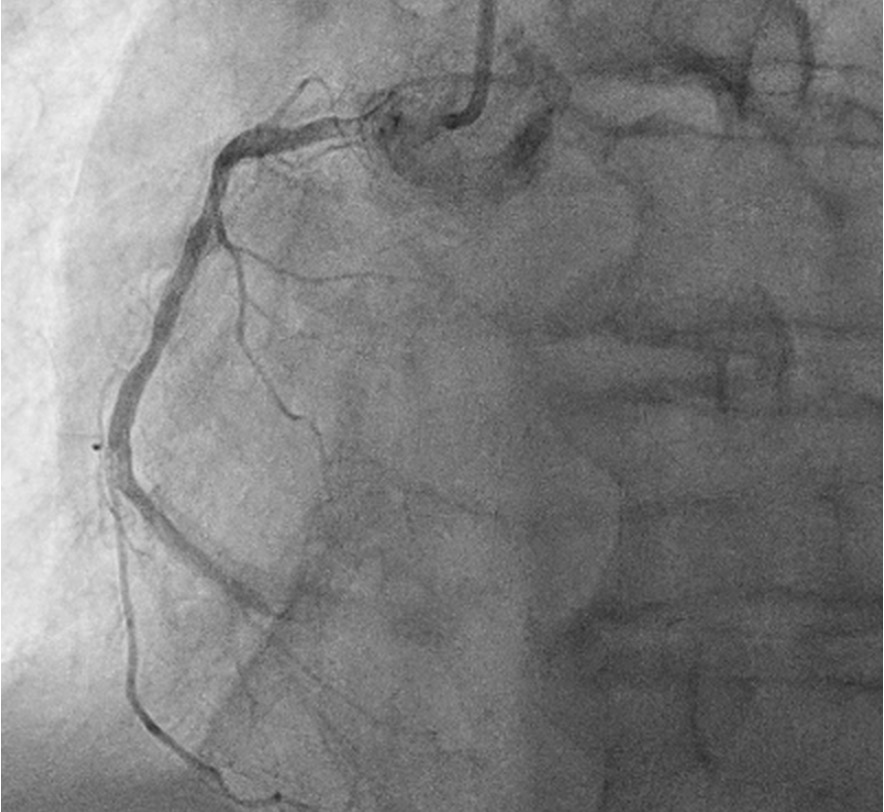

This confirmed severe calcific triple vessel disease. Severe mid LAD diagonal bifurcation stenosis (Medina 1,1,1). Severe LCx ostial and mid stenoses with large ostial calcific nodule. Severe ostial RCA stenosis and distal RCA CTO receiving collateral supply from the septal perforators. CABG was declined due to high surgical risk. After extensive discussions with the patient, his family, and the Vascular Surgical team, high risk vascular and coronary interventions were undertaken.

The Vascular team performed aortoiliac revascularisation to concurrently treat his peripheral vascular disease and allow for femoral access for CHIP. Kissing covered stents were placed from the abdominal aorta to bilateral CIAs and EIAs using the ¡°pave and crack¡± technique with chimney stenting to the IMA. After recovery, single access for Impella CP supported high-risk PCI (SHiP) was performed via the left femoral artery with a 7F sheath through the 14F Impella sheath. Intervention began with the LAD using rotational atherectomy (1.25mm burr) but led to hemodynamic instability despite Impella support, requiring emergency intubation and dopamine infusion. Significant blood loss was noted from the SHiP access due to the inadvertent migration of the PCI sheath proximally, and addressed by repositioning the sheath and transfusion. Once stabilised, the LAD, diagonal, and LCx arteries were treated with rotational atherectomy (1.25mm burr). The LCx had follow up orbital atherectomy, and scoring balloon angioplasty for a large ostial calcific nodule. The left main stem bifurcation was treated with drug eluting stents using OCT guided nano crush technique (3.5/28mm LMS-LAD, 3.5/28mm LCx). The first diagonal and mid LCx were treated with drug eluting balloons (2.5/30mm, 2.5/20mm). Final POT was performed in the LMS (4.0/8mm non-compliant at 18atm). Final OCT and angiography showed satisfactory result with TIMI 3 flow.